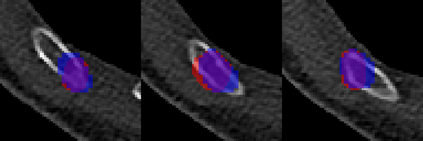

Rib fractures are a common and potentially severe injury that can be challenging and labor-intensive to detect in CT scans. While there have been efforts to address this field, the lack of large-scale annotated datasets and evaluation benchmarks has hindered the development and validation of deep learning algorithms. To address this issue, the RibFrac Challenge was introduced, providing a benchmark dataset of over 5,000 rib fractures from 660 CT scans, with voxel-level instance mask annotations and diagnosis labels for four clinical categories (buckle, nondisplaced, displaced, or segmental). The challenge includes two tracks: a detection (instance segmentation) track evaluated by an FROC-style metric and a classification track evaluated by an F1-style metric. During the MICCAI 2020 challenge period, 243 results were evaluated, and seven teams were invited to participate in the challenge summary. The analysis revealed that several top rib fracture detection solutions achieved performance comparable or even better than human experts. Nevertheless, the current rib fracture classification solutions are hardly clinically applicable, which can be an interesting area in the future. As an active benchmark and research resource, the data and online evaluation of the RibFrac Challenge are available at the challenge website. As an independent contribution, we have also extended our previous internal baseline by incorporating recent advancements in large-scale pretrained networks and point-based rib segmentation techniques. The resulting FracNet+ demonstrates competitive performance in rib fracture detection, which lays a foundation for further research and development in AI-assisted rib fracture detection and diagnosis.